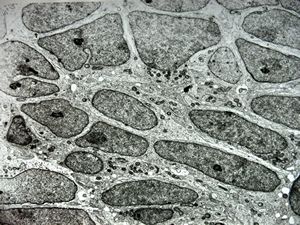

F,12y. | oligodendroglioma

F,12y. | oligodendroglioma

F,12y. | oligodendroglioma